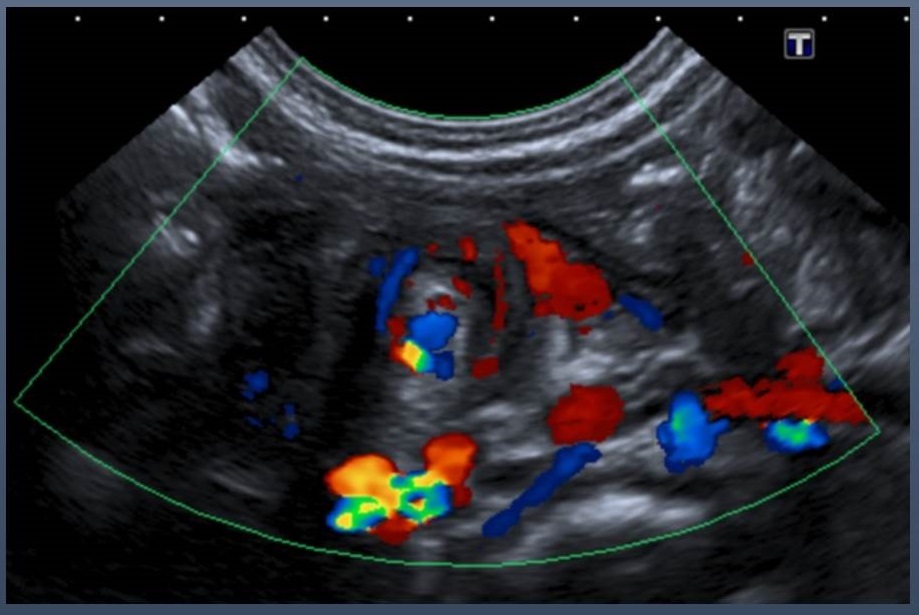

Teniendo en cuenta los hallazgos inespecíficos de la radiografía de abdomen y ante el empeoramiento clínico de la paciente, con incremento de los vómitos biliosos e ictericia de predominio indirecto, se solicita ecografía abdominal. Con la imagen ecográfica. ¿Cuál es su sospecha diagnóstica?

Se visualizan las siguientes tres imágenes ecográficas.